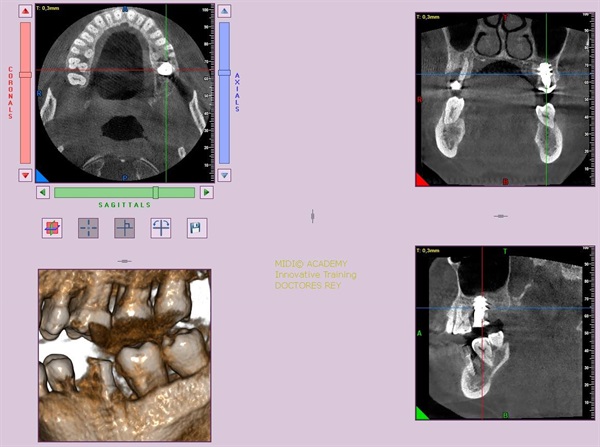

1- Implante de 9 mm de diámetro en maxilar superior post extracción + PRF. MIDI® TECHNIQUE®, no drill.

IMPLANTE EN MAXILAR SUPERIOR post extracción de diametro amplio 9 mm.